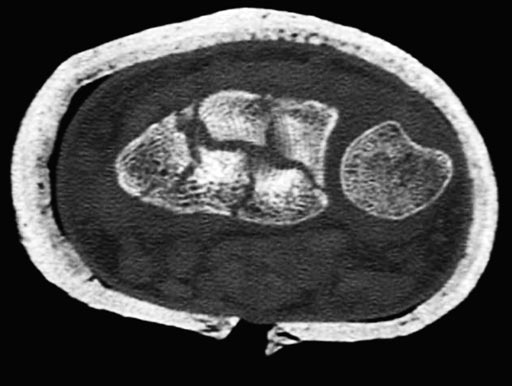

54-year-old female with 23-C3 fracture after fall

External fixator due to severe soft-tissue trauma. Palmar plate 1 week later. .